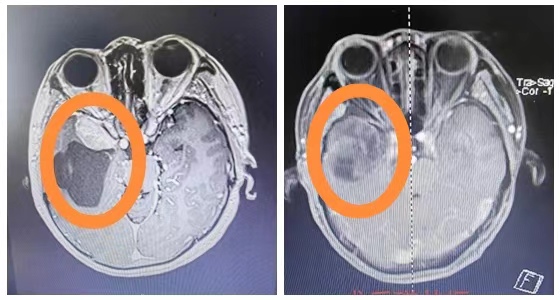

近日,湘雅常德医院神经外科袁贤瑞主任处理完所有病房患者后,带领医疗组匆匆赶往手术室。这是一台非常特殊、极具挑战性的高难度手术,需要为一位患者切除巨大颅眶沟通性复发脑膜瘤。患...